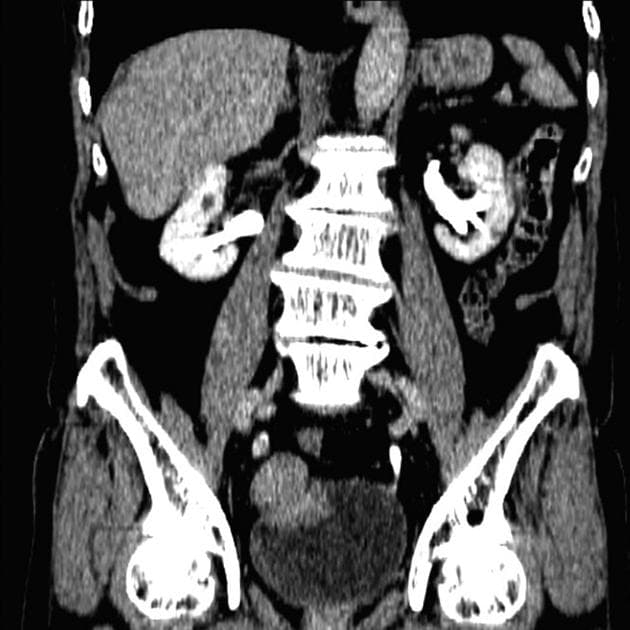

- Một khối ngấm thuốc (enhancing mass) dạng polyp trong lòng mạch (intraluminal) kích thước 40 mm được ghi nhận ở mặt sau bên phải của bàng quang, có liên quan nhưng không gây tắc nghẽn lỗ niệu quản - bàng quang bên phải.

- Lớp mỡ quanh bàng quang còn nguyên vẹn, và không phát hiện bệnh lý hạch (lymphadenopathy) vùng.

- Các nang vỏ thận đơn thuần, nhỏ, không ngấm thuốc với đường kính tối đa 15 mm được thấy ở cả hai thận.

- Vài hạch vôi hóa được thấy ở vùng cạnh động mạch chủ và vùng rốn gan.

Ung thư biểu mô đường niệu, trước đây gọi là ung thư biểu mô chuyển tiếp, chiếm hơn 90% các trường hợp ung thư bàng quang và khởi phát từ lớp biểu mô lót đường tiết niệu. Bệnh có liên quan mạnh với hút thuốc và tiếp xúc nghề nghiệp với các amin thơm. Trên hình ảnh học, khối u thường xuất hiện như một khối ngấm thuốc trong lòng bàng quang, hay gặp ở vùng tam giác hay thành bên bàng quang. Mặc dù chụp CT niệu quản rất tốt để phát hiện và đánh giá đường tiết niệu trên, nhưng nó có hạn chế trong việc xác định chính xác giai đoạn cục bộ. Chụp MRI, với độ tương phản mô mềm cao, cho phép đánh giá tốt hơn mức độ xâm lấn của khối u vào thành bàng quang – yếu tố then chốt trong lập kế hoạch điều trị. Việc không thấy hình ảnh thâm nhiễm hay hạch to quanh bàng quang trong trường hợp này gợi ý khối u chưa xâm lấn sâu (có thể ≤ giai đoạn T2). Các hạch vôi hóa ở vùng cạnh động mạch chủ và rốn gan có thể là dấu hiệu của bệnh u hạt (ví dụ: lao cũ hoặc nấm histoplasma) hơn là di căn, đặc biệt ở các vùng lưu hành bệnh.